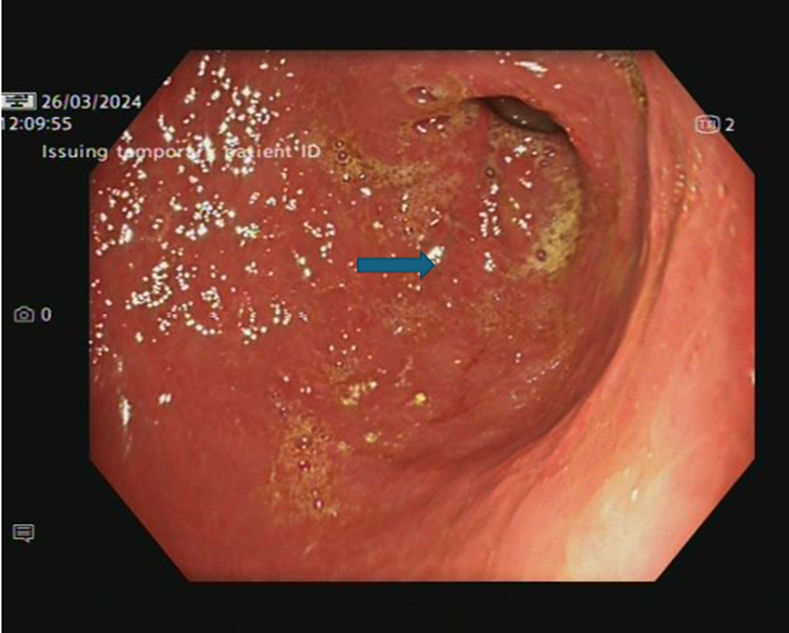

After the completion of three cycles of combined ICIs, the patient developed severe epigastric pain worse with oral intake, associated with nausea and vomiting. He lost 5.6 kg over two weeks; weighed 75.6 kg on admission. Blood tests showed raised inflammatory markers, CRP of 62 mg/L (0-5 mg/L), and raised amylase of 398 U/L (25-125 U/L). CT abdomen and pelvis showed diffusely thick-walled stomach with mucosal hyperenhancement and mural stratification, no peri-gastric fat stranding or lymphadenopathy. There was no evidence of pancreatitis or colitis.Upper gastrointestinal endoscopic examination showed an inflamed Gastro-Oesophageal Junction (GOJ) and pan-gastritis with diffuse inflammation, oedematous and friable gastric mucosa (image 1). Biopsies obtained from GOJ showed nonspecific inflammation, whereas samples obtained from the stomach showed features of ulceration (inflamed denuded granulation tissue).

Image 1: OGD - Stomach lower body (pan-gastritis with diffuse inflammation, oedematous and friable gastric mucosa)